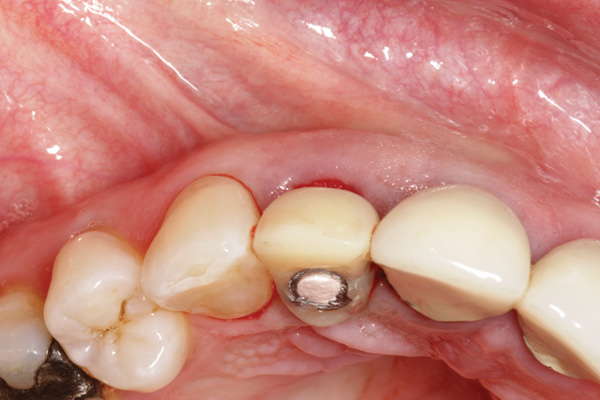

Fig 1. Clinical photograph showing significant issues related to implant midfacial mucosal recession and loss of interdental papillae. This is attributed to incorrect implant positioning (too buccal and too deep); several corrective surgeries resulted in interproximal bone loss, then loss of interdental papillae.

Figure 1

Buccally Positioned Implant

A minimum of 2 mm of facial bone thickness has been proposed as the “critical bone thickness” for the prevention of vertical height loss of the facial plate. It has been reported that when the distance of the buccal shoulder position of the implant to facial bone plate is below this critical thickness, an increased amount of facial bone resorption may be observed, which, in turn, may increase the chance of implant mucosal recession and failure (Figure 1). When the facial bone thickness is more than 2 mm from the implant buccal shoulder position, the likelihood of facial bone loss is decreased and the chance for alveolar bone stability is, therefore, increased.16

Chen and coworkers evaluated the soft-tissue and radiographic outcomes of implants placed in extraction sockets using a nonsubmerged protocol. The result showed statistically significantly higher marginal tissue recession at sites when implants were placed 1.1 mm from the inner buccal socket wall compared with implants placed 2.3 mm from the inner buccal socket wall. Six of the eight implant cases that were buccally positioned had unsatisfactory post-restorative esthetic outcomes. The authors concluded that position of the implant shoulder within the socket is a critical factor for ideal esthetic outcomes; thus, a minimum of 2 mm distance from the implant shoulder to the inner buccal shoulder wall was recommended to prevent implant marginal tissue recession.5